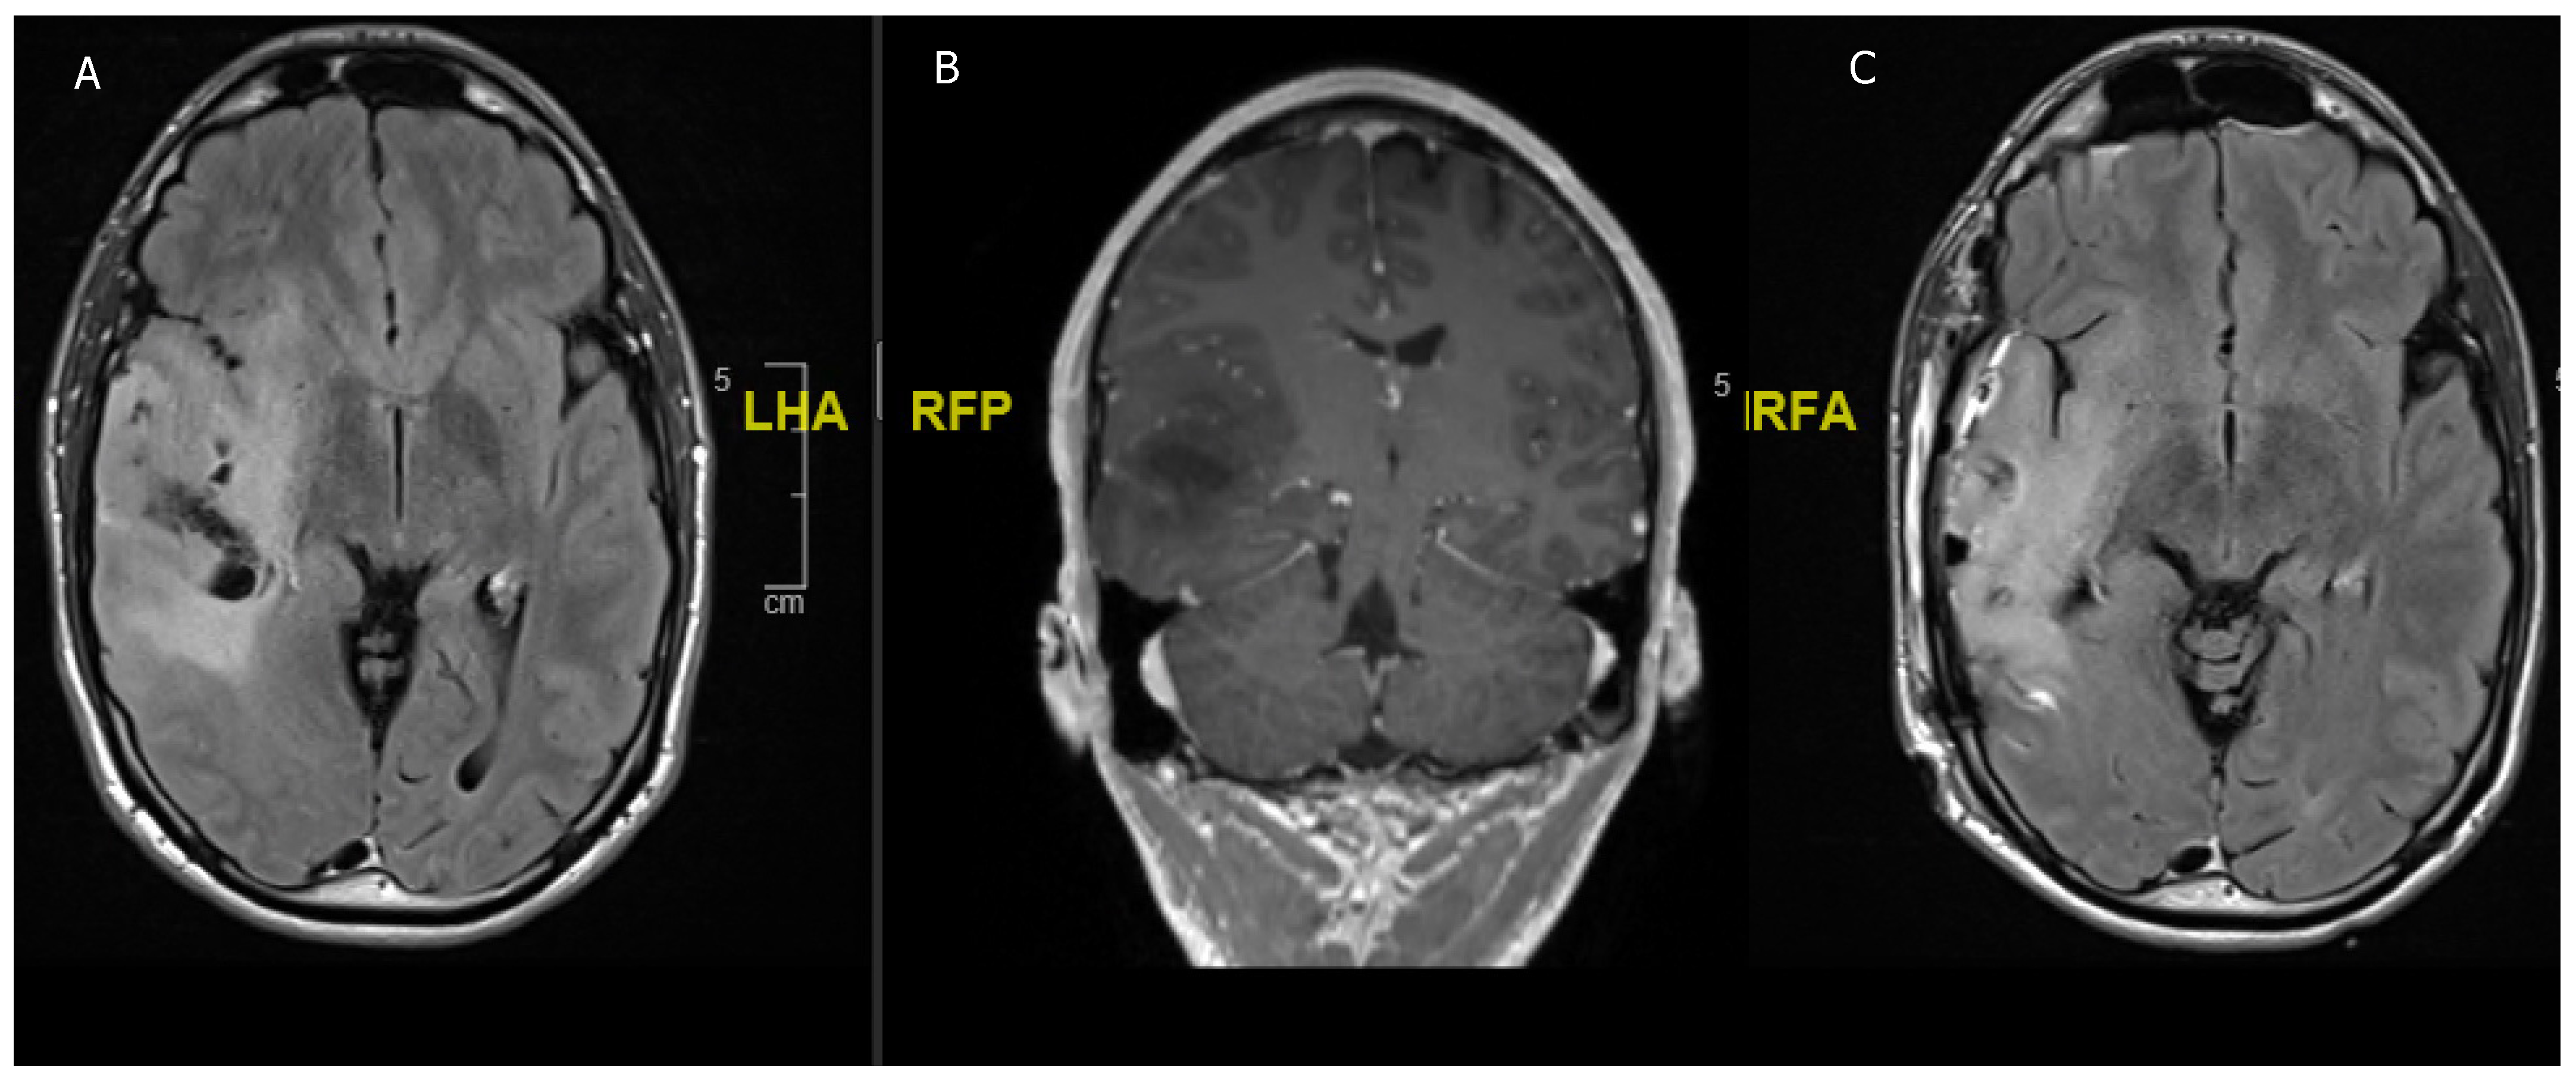

Figure 2. A 16-year-old girl previously diagnosed with TSC and presenting with acute headaches and vomiting. (A) Acute obstructive hydrocephalus and edema due to T2 hypointense lesion in the right frontal horn. (B) Contrast enhancing lesion in the right frontal horn suggestive of SEGA in the context of TSC. (C) Postoperative scan with reduction of ventricular size and showing complete resection of the SEGA.

3.2. Tuberous Sclerosis Complex

The TSC negatively regulates the mTOR pathway, resulting in typical subependymal giant cell astrocytoma (SEGA) in 20% of all patients, and only a small number of reports of SEGA without the clinical features of TSC exist (Figure 2) [31,32]. These tumors mostly occur in children and young adults and are unlikely to occur in adulthood [30]. If they increase in size, they can cause seizures or obstructive hydrocephalus, which is when surgical excision is recommended, although some reports showed that mTOR inhibitors are sufficient for hydrocephalus treatment as well as seizure reduction and control [9]. Moreover, preoperative treatment with mTOR inhibitors can reduce the vascularity of SEGAs, which is beneficial for surgical resection [33,34]. In most cases, the tumor can be medically treated with mTOR inhibitors, which can prevent disease progression in children >3 years of age and has also been shown to be effective terms of cognition, development, and seizure control in TSC children [34,35,36].